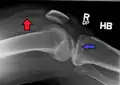

Lipohemarthrosis (presence of fat and blood from bone marrow in the joint space after an intraarticular fracture) seen on X-ray in a person with a subtle tibial plateau fracture -

Lipohemarthrosis due to a tibial plateau fracture -